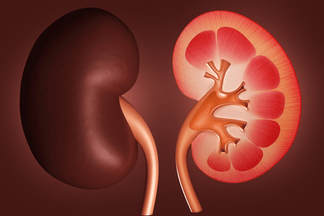

L’insuffisance rénale

L’insuffisance rénale chronique est un état caractérisé par la détérioration de la capacité du rein à filtrer le sang qu’on apprécie par le débit de filtration.

Ce débit exprimé en ml/min est un marqueur de l’évolution de la maladie.

Plus ce dernier diminue plus l’insuffisance rénale s’aggrave.

Les aliments une fois digérés passent dans les intestins.

Des éléments issus de l’absorption intestinale se retrouvent alors dans le sang qui est acheminé vers les reins pour être filtré.

L’insuffisance rénale chronique est un état caractérisé par la détérioration de la capacité du rein à filtrer le sang qu’on apprécie par le débit de filtration.

Ce débit exprimé en ml/min est un marqueur de l’évolution de la maladie.

Plus ce dernier diminue plus l’insuffisance rénale s’aggrave.

Les aliments une fois digérés passent dans les intestins.

Des éléments issus de l’absorption intestinale se retrouvent alors dans le sang qui est acheminé vers les reins pour être filtré.

Il est évident que l’alimentation aura à jouer un rôle fondamental dans l’évolution de l’insuffisance rénale chronique.

Le rein ne devant plus continuer à être soumis à dure épreuve, les aliments difficiles à épurer seront épargnés sans pour autant pousser le patient vers la dénutrition.

L’insuffisance rénale chronique peut aussi s’accompagner d’une perturbation du niveau du fer, du potassium et du phosphore dans le sang.

Toutes ces perturbations peuvent être mieux gérées si les choix alimentaires quantitatifs et qualitatifs sont adaptés.

Le programme alimentaire personnalisé du patient en situation d’insuffisance rénale chronique est global et précis.

Il apporte des informations sur les aliments fréquemment consommés, fixe leurs quantités ainsi que leurs répartitions journalières.